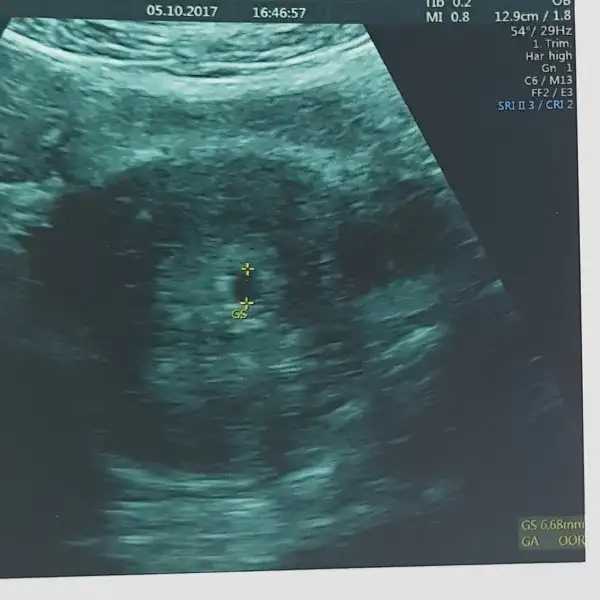

Kızlar gördüm çok şükür tek kese . Biliyorsunuz bende rahim ağzı yetmezliği olduğu için çok rahatladım inş yine de rabbimden hayırlısı. Doktorumuz kesenin şeklini de büyüklüğünüde çok beğendi. Bir dahaki haftaya perşembe yine çağırdı :) darısı tüm grubun başına inş hala elim ayağım titriyor